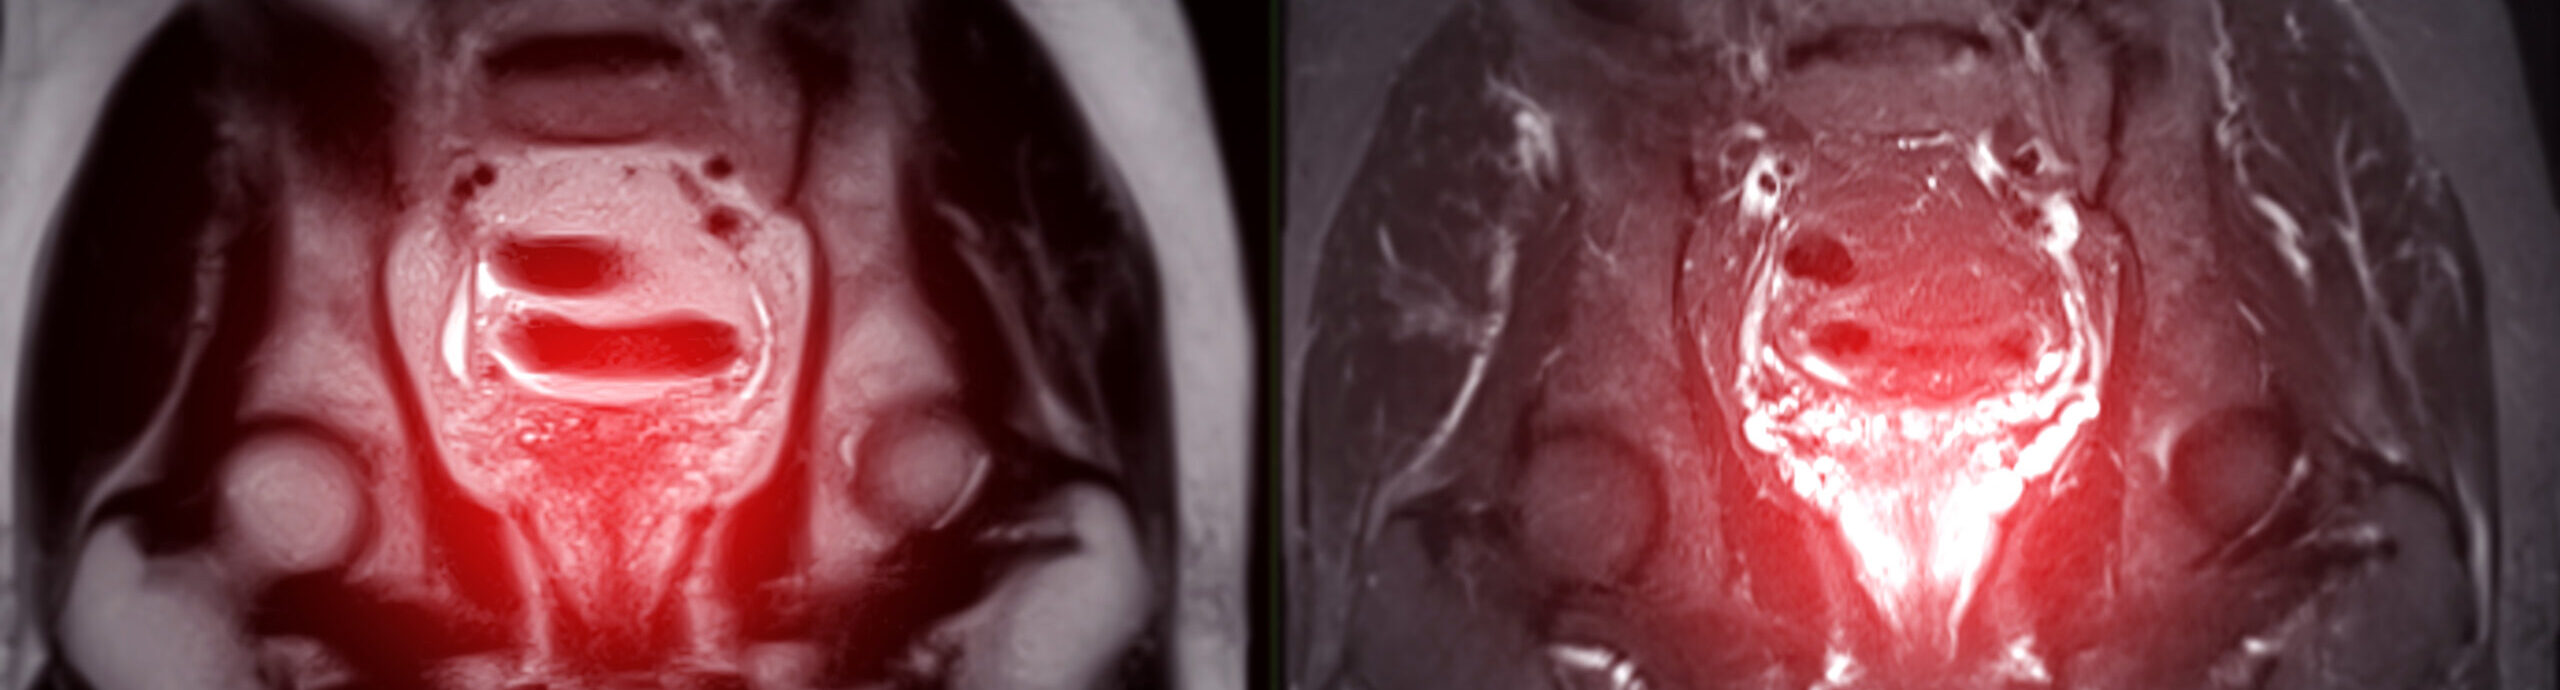

At Vitus Private Clinic, advanced imaging is used to assess recurrence comprehensively. This includes MRI to evaluate localized disease and PSMA PET/CT with gallium-68 to detect metastatic spread throughout the body.

Together, these tools allow the extent of recurrence to be defined accurately and treatment to be planned on an individual, case-by-case basis.

- Findings on MRI and PSMA PET imaging: Advanced imaging is used to determine where recurrence is located and how it behaves, helping guide whether a single focal treatment or a broader strategy is most appropriate.